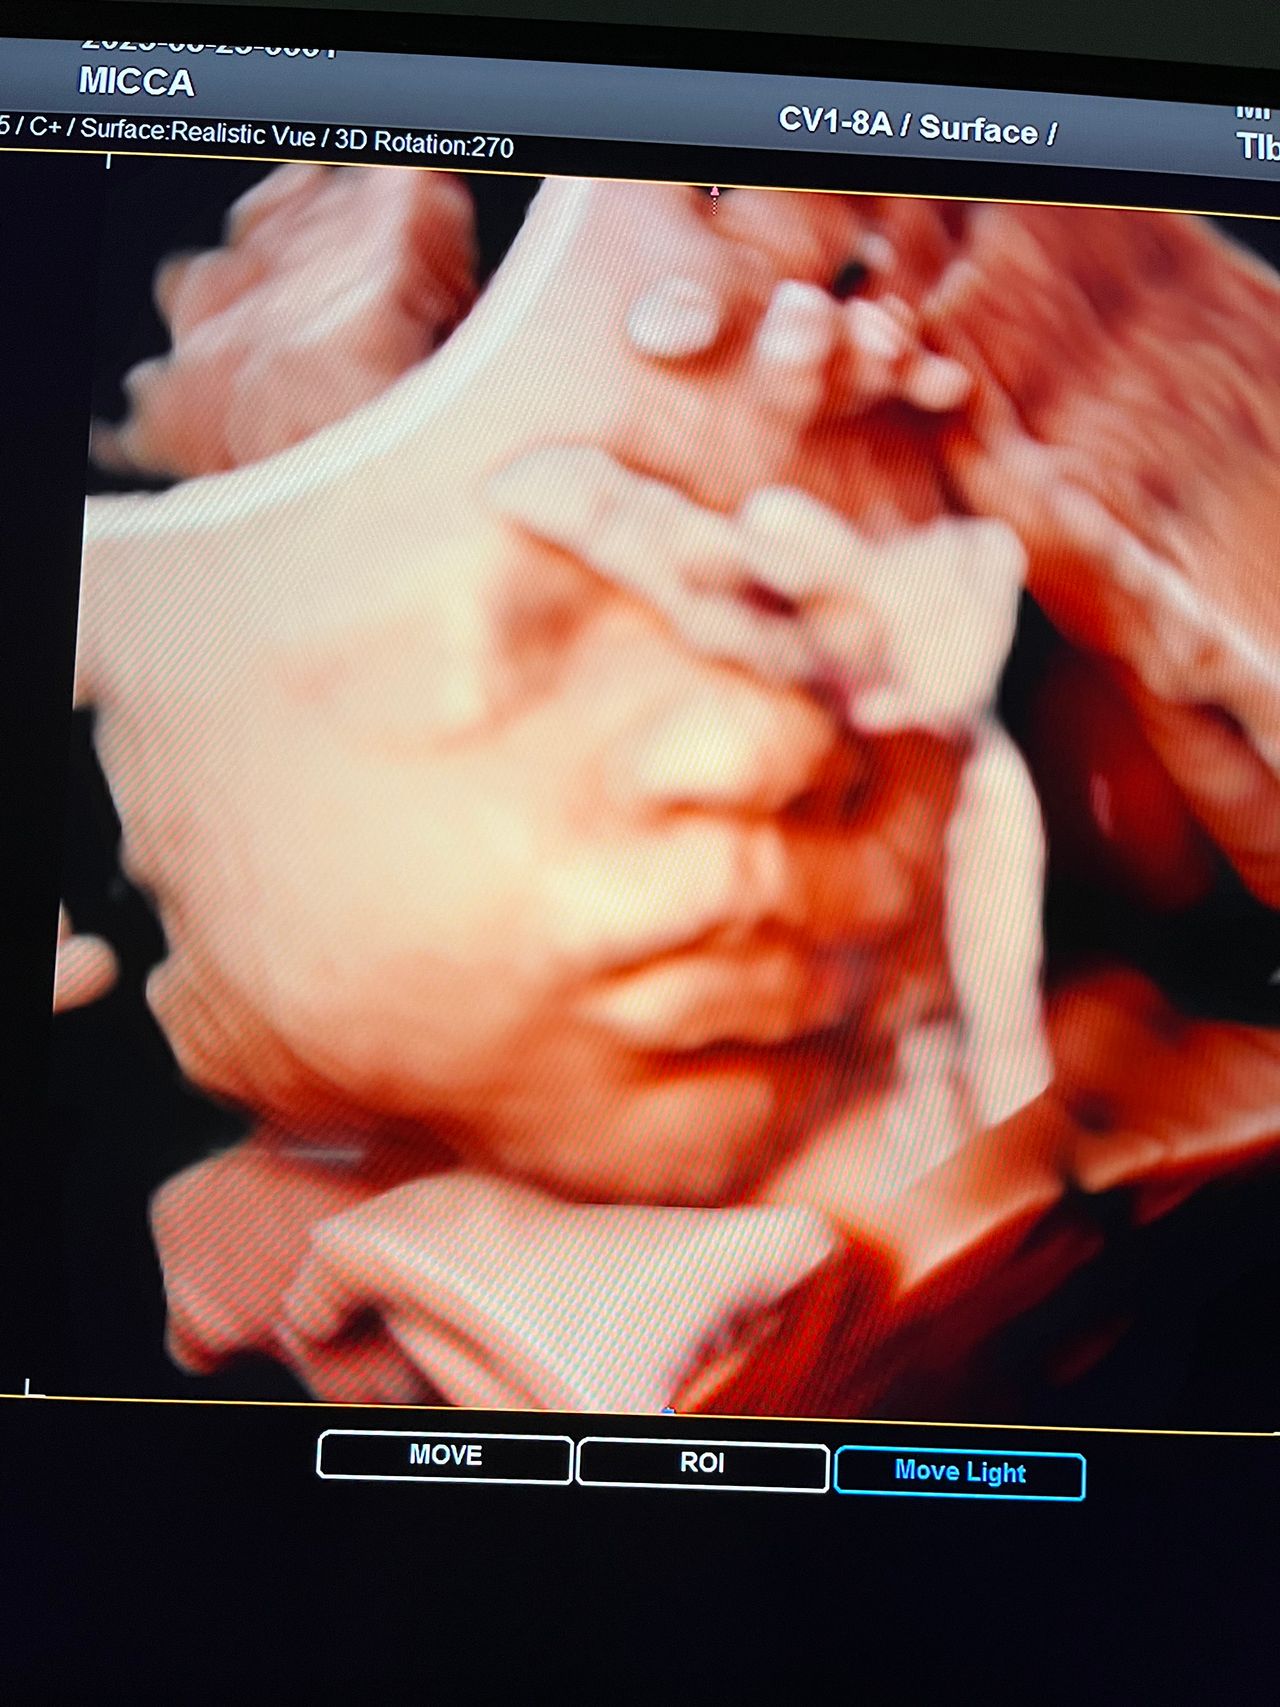

Attualmente lavoro come Dirigente medico nella SC di Ostetricia e Ginecologia dell'Ospedale Michele e Pietro Ferrero di Verduno, mi occupo prevalentemente di screening prenatale, ecografia ostetrica del I trimestre( misurazione translucenza nucale,NT), ecografia morfologica del II trimestre, ambulatorio pregresso taglio cesareo, ecografia ostetrica 3D. Seguo le gravidanze fisiologiche e quelle ad alto rischio , presto servizio in sala parto. Eseguo visite ginecologiche di I-II livello in regime ambulatoriale, counseling contraccettivo ed eventuale prescrizione pillola, inserimento spirale (IUD), dispositivo sottocutaneo (Nexplanon).

Foto e video